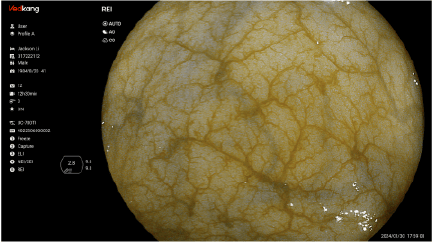

Dual Light Display Educational tool to shorten learning curve on optical chromoendoscopy image, by si- multaneously comparing white light image and chromoendoscopy image in real time